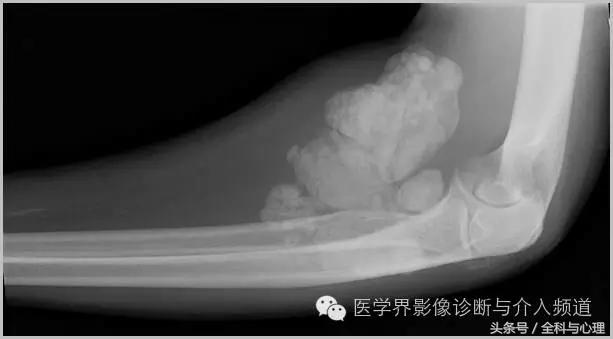

4、痛风石

为尿酸盐沉积形成,发生在关节周围软组织、包括韧带、肌腱、滑囊,眼、耳、鼻、喉、皮肤, 50%的钙化为X线平片可见。

痛风石,可见软组织肿胀及钙化灶。